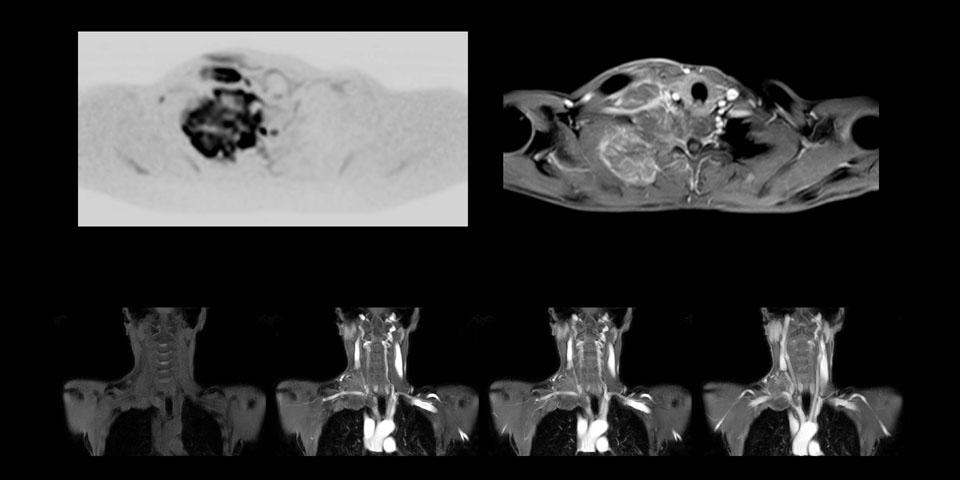

MR-Untersuchung einer 61-jährigen Patientin mit einem malignen Lymphom mit diffusionsgewichteter Ganzkörper-MRT sowie PET. Auf den gezeigten Bildern ist die Auflösung mit der diffusionsgewichteten MRT besser als mit der PET, die eine Darstellung der kleinen Beckenläsionen ermöglicht; im Halsbereich ist praktisch keine Verzerrung zu erkennen.